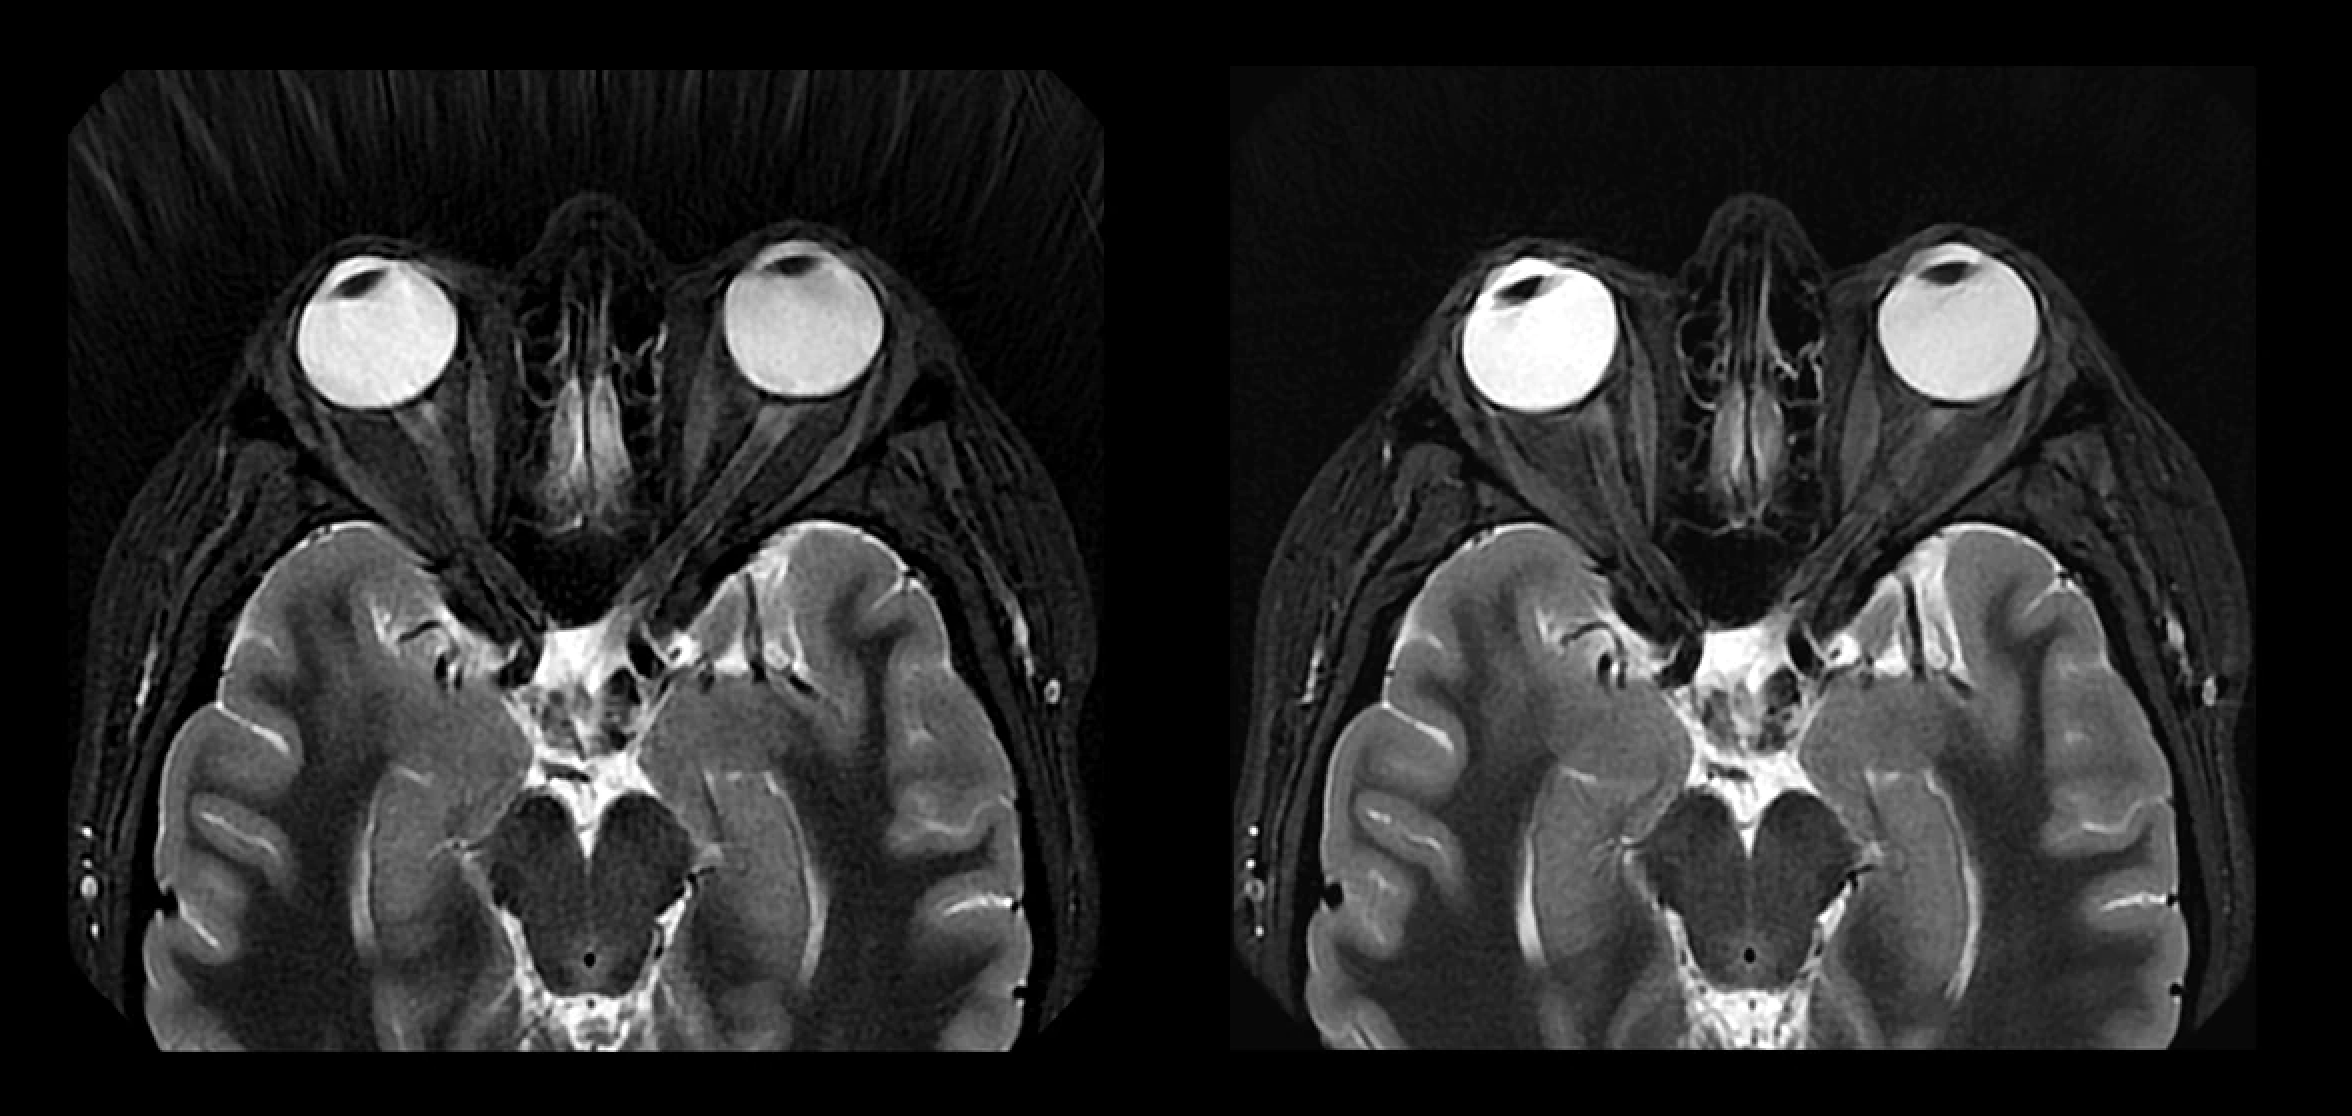

Rancid – Indestructible – CD (Digipak, Album), 2003, GE Healthcare's AIR Recon DL Receives FDA Clearance of 3D,

GE Healthcare's AIR Recon DL Receives FDA Clearance of 3D, New) PACCAR 350603 DEF Coolant Loop Sending Unit Fits 2018,